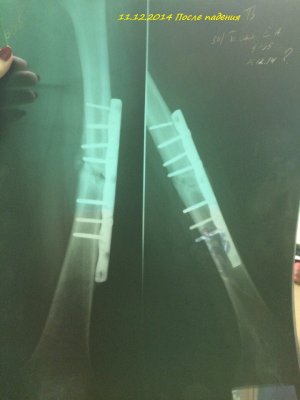

Здравствуйте! Мне 19 лет. 16.07.2014 года у меня случился закрытый перелом с/3 правого бедра со смещением. Произошло это так: я решила заниматься бегом. Каждый день бегала по стадиону минут 30-40. Получилось так, что я бежала, потом споткнувшись правой ногой, вернее как только я споткнулась, услышала хруст и упала на левую сторону. Сначала вообще не поняла, что произошло. Попыталась пошевелить ступней, особых болевых ощущений не испытала и решила попробовать встать, как только я попыталась поднять ногу, я увидела как у меня в бедре "шевелятся" кости. В итоге вызвали скорую, сделали рентген (все снимки я загрузила), поставили спицу под б/берцовую кость, почти под коленом, и я лежала 6 дней на вытяжке. 22.07.2014 года был проведен Экстрамедуллярный остеосинтез правого бедра пластиной АО (все пишу из выписки медицинской карты)Причем, прошу заметить на снимках может быть не видно, во время операции обломалось сверло, и пластину не закрепили по краям, я, конечно, мало что понимаю. 4.08.2014 года мне наложили гипс и отправили домой. 15.09.2014 года сняли гипс, я стала постепенно разрабатывать ногу, ходить, примерно 1.10.2014 года я стала ходить с тростью, все вроде бы шло на поправку. 23.10.2014 года меня выписали, и я уехала учиться в ВУЗ. Примерно вначале декабря я упала с лестницы(примерно со 2-ой ступеньки, при этом все это время я ходила с тростью). Стала болеть нога, я пошла в больницу, вновь снимок. Сказали все нормально-срастается. Назначили магнит(10 дней), отходила я на магнит. Все стало нормально, после НГ я могла ходить без трости, немного хромала, носила ее с собой, и когда уставала-ходила с ней. Вначале марта, примерно с 5-ого числа, стали мучить очень сильные боли, причем болело колено, очень тянуло берцовые кости, иногда беспокоило место перелома, вновь иду в больницу, опять снимок. И УЖАС! На снимке видно, как у меня кривится кость, чуть ли не ломаясь пополам, и переломана пластина. Мне говорят, что нужно делать операцию, врач сказал, что пластину не будут ставить повторно, эту уберут, все почистят и поставят штифт.

Прошу Вас, скажите, почему могла сломаться пластина? И подходит ли в моем случае установка штифта? Каково Ваше мнение по этому поводу. Заранее благодарю!